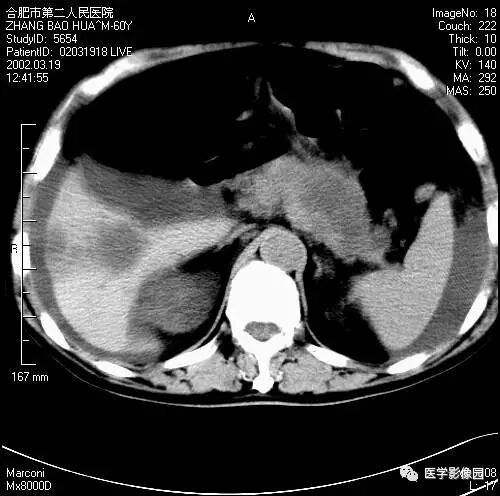

图6-4-10胰腺癌

A.CT平扫胰头球形扩大,

其内呈低密度(↑);

B.增强扫描动脉期,

胰头癌低密度显示更清晰